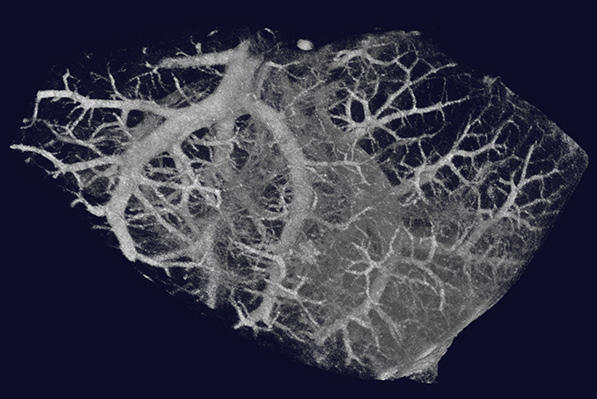

改良されたX線源(20〜100kV、20W)を搭載したGX IIIは、軟組織のような低密度のサンプルから骨のような高密度の物体まで、幅広いサンプルに対して高いX線透過性を実現しています。その結果、シグナル対ノイズ比が向上し、より優れた画像品質が得られます。

GX IIIは、マウスから小型ウサギまでのさまざまな種のin vivoイメージングだけでなく、より高解像度なex vivo イメージングも可能となり、さまざまなサンプルをより最適な測定方法で撮影できる幅広い柔軟性を提供します。